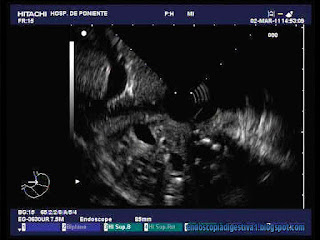

ENDOSCOPIA DIGESTIVA: Pancreatitis crónica calcificante moderada-severa. Diagnóstico por USE radial